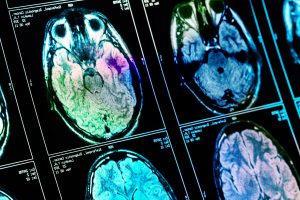

Mehr erfahren zu: "PET; PET/CT zur Unterstützung von Therapieentscheidungen bei bestimmten malignen Lymphomen werden Krankenkassenleistung" PET; PET/CT zur Unterstützung von Therapieentscheidungen bei bestimmten malignen Lymphomen werden Krankenkassenleistung Der Gemeinsame Bundesauschuss (G-BA) hat den Einsatz der Positronenemissionstomographie (PET) /Computertomographie (CT) zur Unterstützung von Therapieentscheidungen bei bestimmten malignen Lymphomen (Krebserkrankungen des lymphatischen Systems) als Leistung der gesetzlichen Krankenkassen in […]

Mehr erfahren zu: "Nur beim Radiologen: MRT-Untersuchungen für gesetzlich Versicherte" Nur beim Radiologen: MRT-Untersuchungen für gesetzlich Versicherte Für eine Magnetresonanztomografie (MRT) müssen nach wie vor gesetzlich Versicherte zum Radiologen. Die 1. Kammer des Ersten Senats des Bundesverfassungsgerichts hat die Klage eines Kardiologen mit Zusatzweiterbildung „MRT – fachgebunden“ […]

Mehr erfahren zu: "Beste Bildgebung im Bergmannsheil: Zwei Magnetresonanztomografen der neuesten Generation installiert" Beste Bildgebung im Bergmannsheil: Zwei Magnetresonanztomografen der neuesten Generation installiert Die Modernisierung des BG Universitätsklinikums Bergmannsheil geht weiter voran: Im Neubau des Klinikums wurden jetzt zwei neue Magnetresonanztomografen (MRT) installiert. Sie erzeugen präzise Schnittbilder des Körpers, liefern höchste Bildqualität und […]